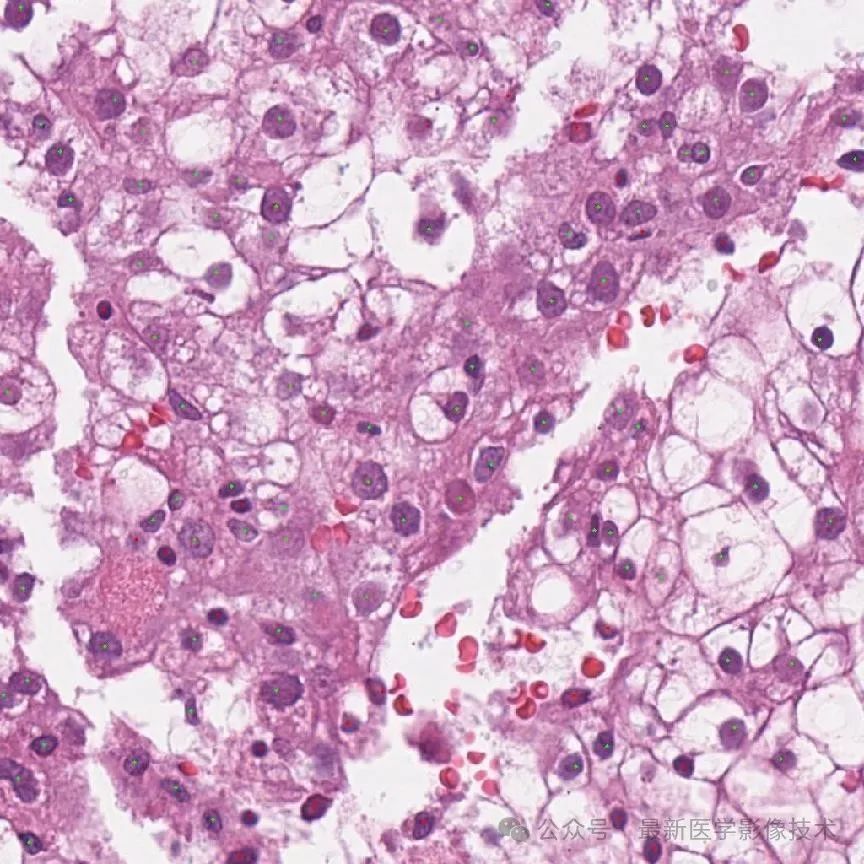

4、验证集部分检测结果

第一个是金标准结果,第二个是网络检测结果。

细胞检测结果